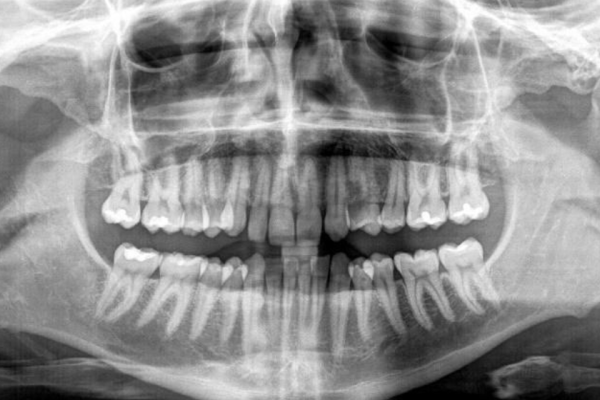

Manejo quirúrgico y restaurador de un implante en área estética y evaluación volumétrica tras un injerto de tejido conectivo desepitelizado. Descripción de un caso clínico

El reto del abordaje quirúrgico en la rehabilitación sobre un implante unitario en un caso de alto requerimiento estético del sector anterior. Descripción a propósito de un caso

The challenge of the surgical approach in the rehabilitation of an anterior sector unitary implant in a case of high aesthetic requirements; case report